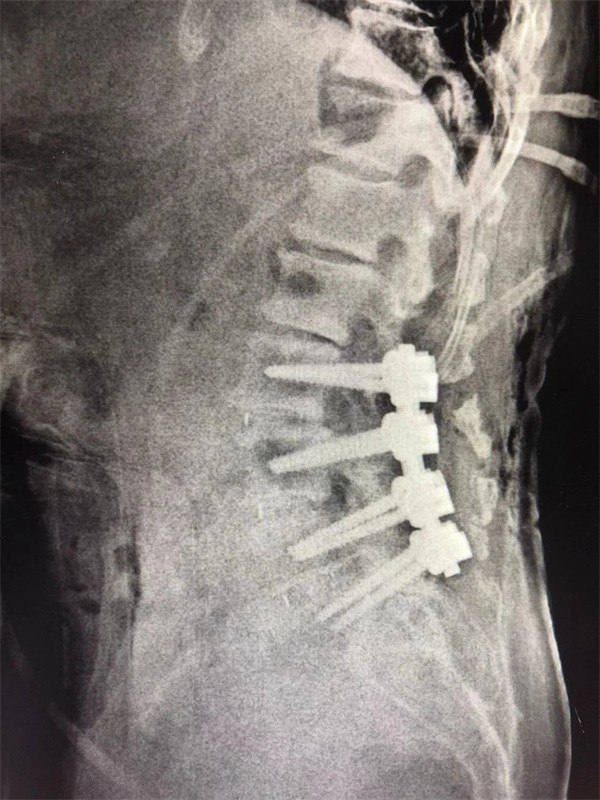

手術(shù)后↓

戈才華主任團隊討論病情及手術(shù)風險,并與麻醉科醫(yī)生多次討論術(shù)中麻醉風險,經(jīng)過詳盡周密的布置之后,最終給阿婆在全麻下進行腰3/4,4/5,腰5/骶1腰椎椎體間融合術(shù)。

術(shù)后阿婆腰痛伴雙下肢疼痛明顯緩解,術(shù)前疼得晚上睡不著覺的情況不再出現(xiàn)。阿婆和家屬連聲道謝,對醫(yī)生的治療技術(shù)和服務(wù)贊不絕口。